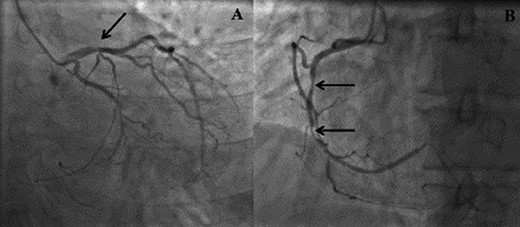

(A) Right anterior oblique (RAO) view demonstrating distal left anterior descending disease. (B) Left anterior oblique (LAO) view demonstrating mid right coronary artery disease.

We report on a 57-year-old gentleman who initially presented with a 6-month history of heavy central chest pain, back and shoulder pain and shortness of breath on exertion (New York Heart Association Classification (NYHA) III, Canadian Cardiovascular Society Angina Classification (CCS) II). He suffered an inferior myocardial infarction in 2007 and has a known bicuspid aortic valve under follow-up. Risk factors for ischaemic heart disease include current smoking and a positive family history of heart disease on his maternal side. On admission, a transoesophageal ECHO (TOE) (Fig. 1) and cardiac magnetic resonance imaging (MRI) (Fig. 2) were carried out and demonstrated the bicuspid aortic valve with a mixed stenosis/regurgitation pattern (moderate–severe) (Fig. 1A). In addition, marked left ventricular dilatation and an inferior LVA extending from the base to the mid-cavity of the left ventricle measuring 4.5 cm across the orifice (Fig. 1B) were seen. The aneurysm was thin walled, with dyskinetic motion with evidence of a dense thrombus adherent to the wall. The inferior wall was noted to be akinetic and non-viable. Preoperative LVEF was 60%. The angiogram showed stenosis of the right coronary artery (Fig. 3B) in the mid-segment together with distal left anterior descending disease (Fig. 3A).